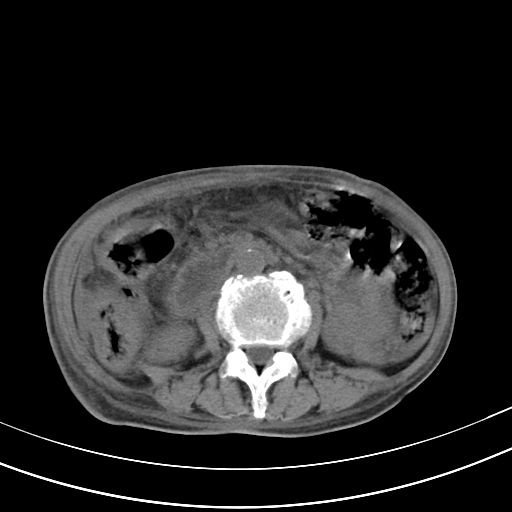

病人上腹部胀痛拌全身黄染八天

右侧少量胸水,胆囊增大,肝内胆管扩张,肝门部结构杂乱,建议增强。

肝内胆管及胰管扩张考虑为胰头区占位,肝门淋巴结增多,肝内多发低密度影,考虑为转移。门脉高压,脾大,胆囊大。

肝内胆管及胰管扩张,胰头增大考虑为胰头区占位,肝门淋巴结增多,考虑为转移。建议增强,脾大,胆囊大,壁厚,慢性胆囊炎。胃壁好像也增厚,且有一肿物。

1)考虑胰头癌并胆系低位梗阻;建议行ct增强扫描检查。2)慢性胆囊炎。3)脾大。4)少量腹水。5)双侧少量胸腔积液。